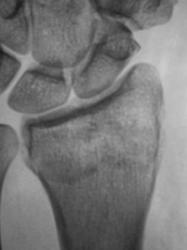

Пациент направлен врачом общей практики (ВОП) на рентгенографию лучезапястного сустава с диагнозом "Перелом?". Произведено стандартное исследование лучезапястного сустава. Выявлен перелом лучевой кости в типичном месте почти без смещения отломков, перелом локтевой кости в области основания шиловидного отростка с незначительным смещением отломков по ширине. Возникает подозрение на разрыв дистального луче-локтевого сочленения. Ваше мнение коллеги?